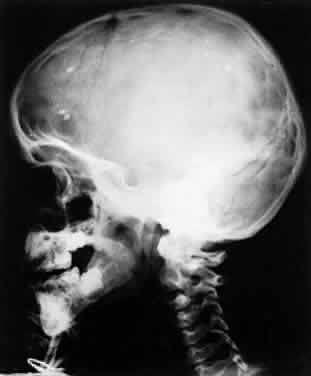

Clinical manifestations of congenital toxoplasmosis consist of retinochoroiditis, fever, hepatosplenomegaly, lymphadenopathy, jaundice, skin rash, petechiae, myocarditis, encephalitis, and retinochoroiditis. Patients may later develop hydrocephaly or microcephaly, cerebral calcifications, convulsions, and psychomotor retardation. The most common clinical manifestation of congenital toxoplasmosis is retinochoroiditis. The microcephaly, which is a severe form of disease, may occur after injury to the brain by the infectious process. The calcifications tend to be scattered throughout the brain substance in toxoplasmosis (Fig. 5), whereas in cytomegalic inclusion disease the calcifications tend to be paraventricular. This finding, however, varies and is not absolute.

Fig. 5. Cerebral calcification in congenital toxoplasmosis. (Christenson L, Beeman H, Allen A: Cytomegalic inclusion disease. Arch Ophthalmol 57:90, 1957)

Ultrasound, CT scan, and MRI have been used to detect signs of intrauterine toxoplasmic infection in newborns.112 The radiologic signs were scarce, and ultrasound findings combined with maternal serologic study were found to be significantly related to the clinical outcome. X-ray of the skull may help to detect intracranial calcification in cases of congenital toxoplasmosis.